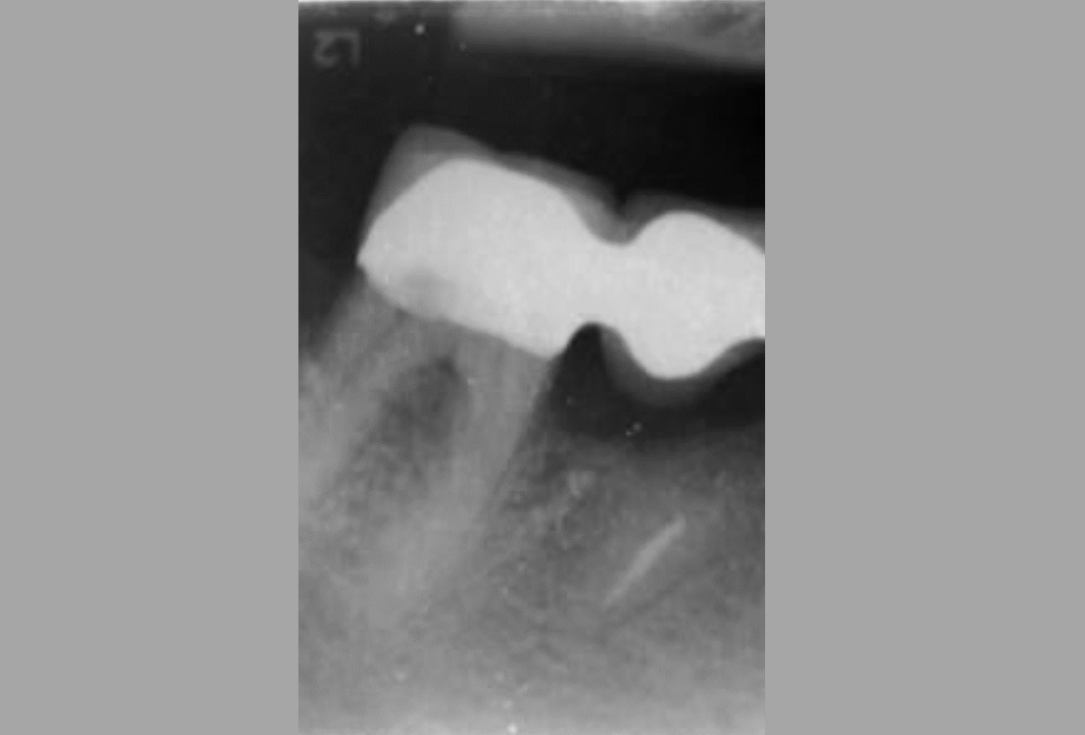

01/06 - Pre-operative radiographic view.Intrabony defect treated using Straumann® Emdogain®, cerabone® and Jason® membrane - Dr. D. B. Hangyási

Pre-operative radiographic view.